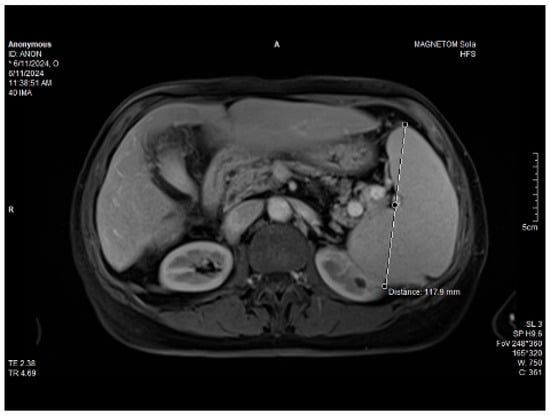

Abdominal MRI study confirmed the hepato-splenomegaly, ascites and the patency of the portal vein system. In addition, small veno-portal shunts were highlighted at the periphery of both hepatic lobes. Various MRI features are depicted in Figure 6, Figure 7, Figure 8 and Figure 9.

Figure 6. MRI featuring perihepatic and perisplenic ascites.

Figure 7. MRI: splenomegaly.

Figure 8. Massive thickening of the gallbladder wall, MRI features.